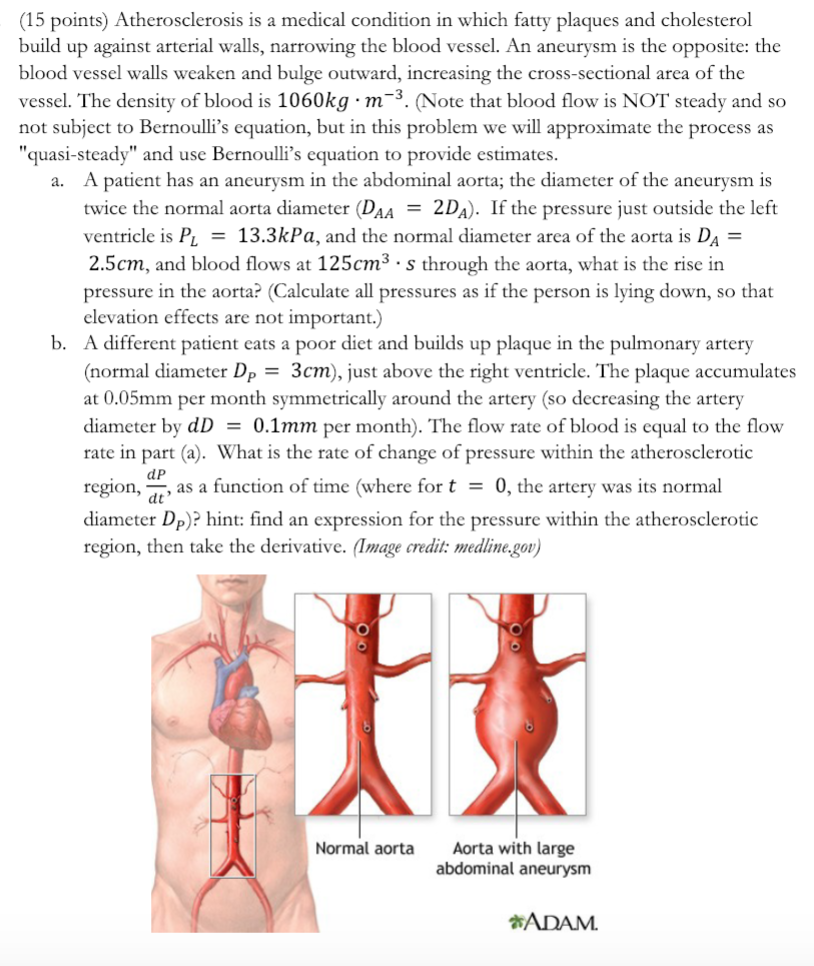

Solved (15 points) Atherosclerosis is a medical condition in | Chegg.com